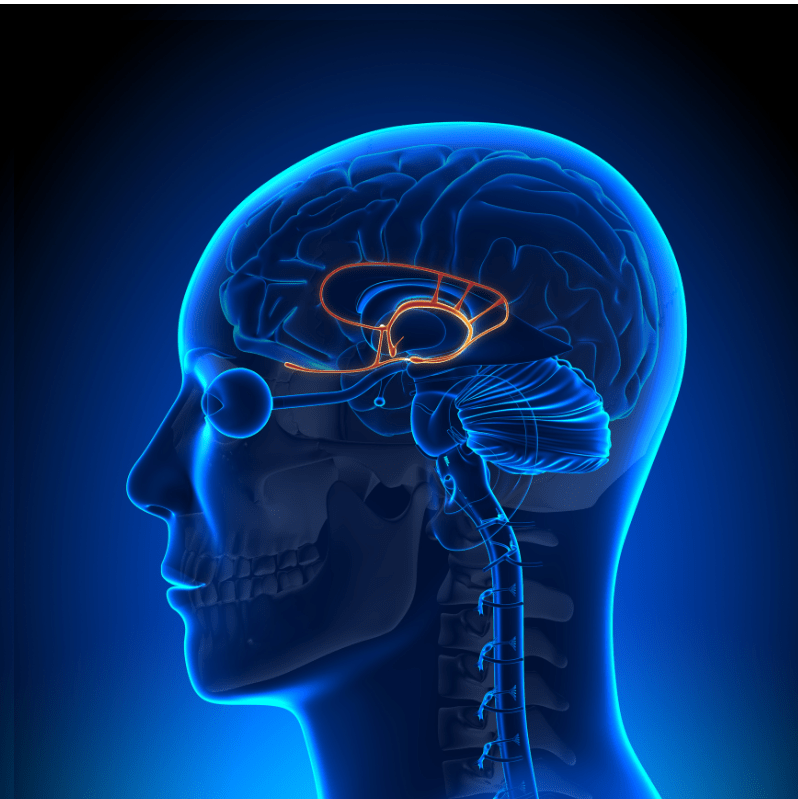

L’hypnose, l’EMDR, la Pnl et d’autres outils puissants vous aideront à réguler, et désamorcer la charge émotionnelle, afin d’éviter les reviviscences (cauchemars par exemple, ou images qui reviennent même en journée, entraînant des symptômes de stress ou de détresse, ou envie d’évitement (de lieux, de situation etc.). Après quelques séances (comptez au minimum 2 séances, parfois bien plus), les symptômes (angoisses, stress, palpitations etc.) s’apaiseront afin que vous puissiez retrouver une vie normale.

Je mets à votre disposition différentes méthodes, comme l’hypnose thérapeutique, l’Emdr et les stimulation bilatérales alternées (kinesthésiques et auditives), la Pnl, et des stratégies de psychothérapie, afin de vous aider à retrouver le chemin de la résilience, d’envisager une vie plus sereine et vous libérer du poids du passé.